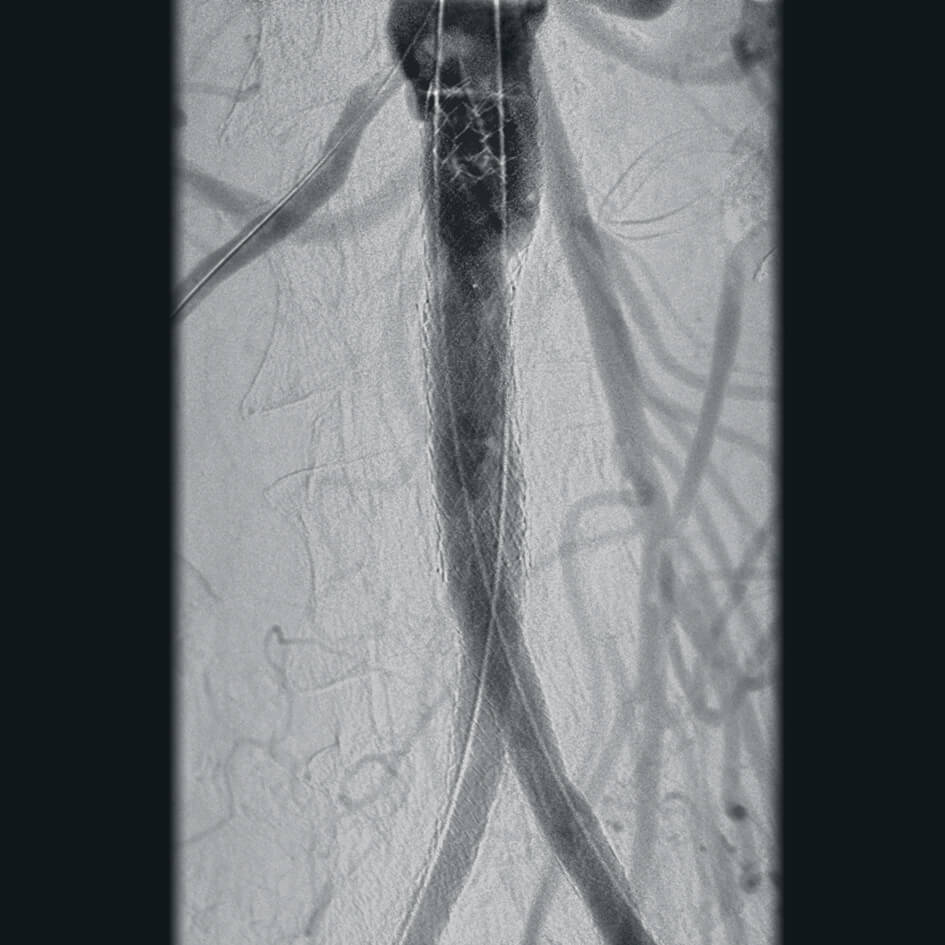

- эндоваскулярная хирургия,

- программный пакет для сосудистой хирургии,

- субтракционная ангиография с применением СО2.

Полное отсутствие искажений снимков в сочетании с высоким динамическим диапазоном широко востребованы как при сложных операциях в нейрохирургии, сосудистой хирургии, инвазивной радиологии, так и в гибридных областях применения, а также в ортопедии, травматологии. В сосудистой хирургии особенно важны высокий динамический диапазон и пространственное разрешение, обеспечивающие детальную визуализацию даже мельчайших сосудов. Специализированное программное обеспечение SmartVascular позволяет проводить настройку системы для васкулярных операций и сосудистой хирургии.

Впервые в мировой практике в Vision RFD 3D используется невероятно компактный моноблочный генератор для импульсной рентгеноскопии с увеличенной резервной мощностью и вращающимся анодом рентгеновской трубки для улучшения качества изображений при минимальной интенсивности облучения. Продолжительность импульсов можно регулировать в диапазоне от 7 до 40 мс, что существенно повышает четкость снимков. Vision RFD 3D отлично подходит для использования в клинических процедурах типа: чрескожная транслюминальная коронарная ангиопластика или коронарная ангиография.